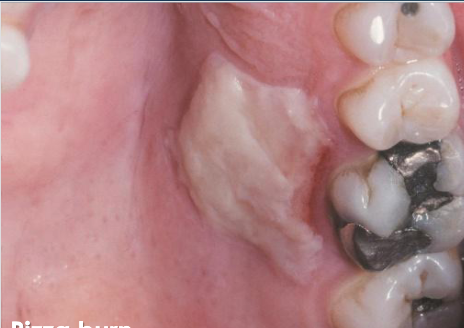

chemical burn

necrotic pseudomembrane that can be scraped off, due to chemical sensitivity

thermal burn

due to contact with hot food/beverage